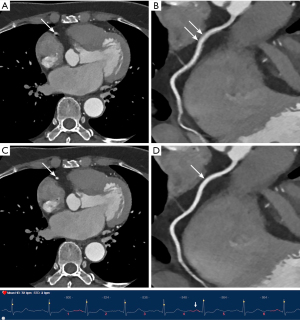

Similarly, the use of MCR significantly improved subjective image quality and interpretability in both subgroups, with a more evident difference observed in the high HR and/or arrythmias group. In the low HR group, although subjective image quality scores performed with MCR displayed a consistent superiority, no significant difference was noted in terms of interpretability by every coronary artery (all P>0.05). Conversely, in the high HR and/or arrythmias group, the application of MCR resulted in a remarkable improvement in interpretability at all levels. Concerning the major three coronary arteries, the greatest benefit in interpretability improvement was found for RCA, where the proportion of arteries considered non-interpretable decreased dramatically from 70.3% to 8.1% (P<0.001). Figures 3-6 display four representative clinical cases, among which Figure 6 contains invasive coronary angiography image.

MCR showed remarkable improvements in subjective image quality and interpretability in the overall population and both subgroups, an observation that was particularly evident for the higher HRs (HR ≥75 bpm), which is consistent with previous research (15,16). Notably, the inclusion criteria of patients with arrhythmia were less strictly controlled in the present study, rendering our study population relatively more representative for an actual clinical scenario. Motion artifacts produced by a constantly beating heart deteriorates the delineation of coronary arteries, especially for patients with AF characterized by high HR and high HR variability, which have traditionally been excluded from CCTA examinations (32,33). However, CCTA with the application of MCR achieved sufficient image quality, tremendously reducing the ratio of segments deemed non-interpretable from 30.0% to 1.9% in the high HR and/or arrythmias group.

Analysis by segments revealed that the mid-segment of the RCA yielded the lowest image quality because it is perpendicular to the scanning plane leading to the most severe motion artifacts (34). As a result, the greatest benefit from MCR was obtained in this segment. In the low HR group, despite the continuous superiority of subjective image quality scores with the use of MCR across all evaluated segments, there was no significant difference regarding interpretability for every coronary artery. A plausible explanation for this result is that patients with lower HRs are less susceptible to motion artifacts due to possessing having relatively longer diastolic phase of the cardiac cycle, usually referred to as the “cardiac quiescence” phase (35). Consequently, there would be less room for the motion-correction algorithm to enhance image quality. Additionally, the sample size of this subgroup was limited, which might be an important factor contributing to the lack of statistical significance. Therefore, MCR showed limited improvements in this regard.